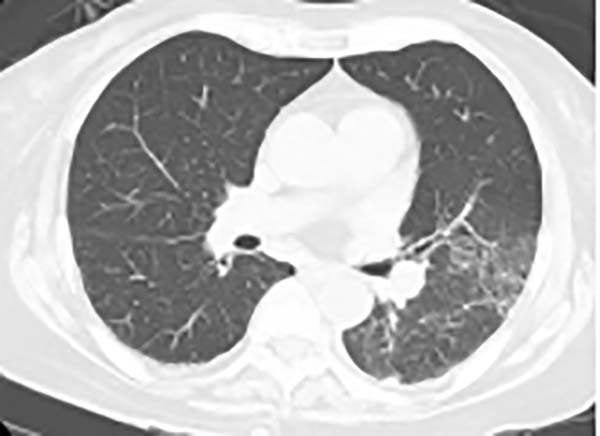

治疗效果速览

三、胸CT有哪些特点?

胸CT以炎性病变始于单侧肺下叶多见,加重后累及双侧肺叶,上下肺均可受累,主要表现为大片状实变影,可合并小片状磨玻璃影、结节影,以胸膜下分布为主,可见“支气管充气征”“细网格征”“晕征”,常伴胸腔积液,可伴淋巴结肿大。